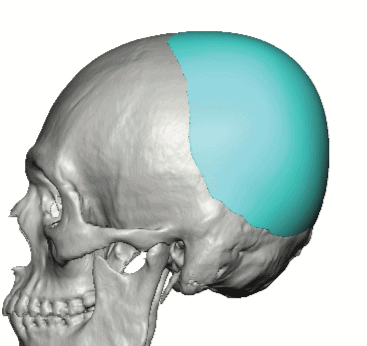

Patient 49

Desire for further skull augmentation after a primary skull implant.

Five years after an initial custom skull implant placement a new custom skull implant that increased the volume by 35% was placed.

Desire for further skull augmentation after a primary skull implant.

Five years after an initial custom skull implant placement a new custom skull implant that increased the volume by 35% was placed.